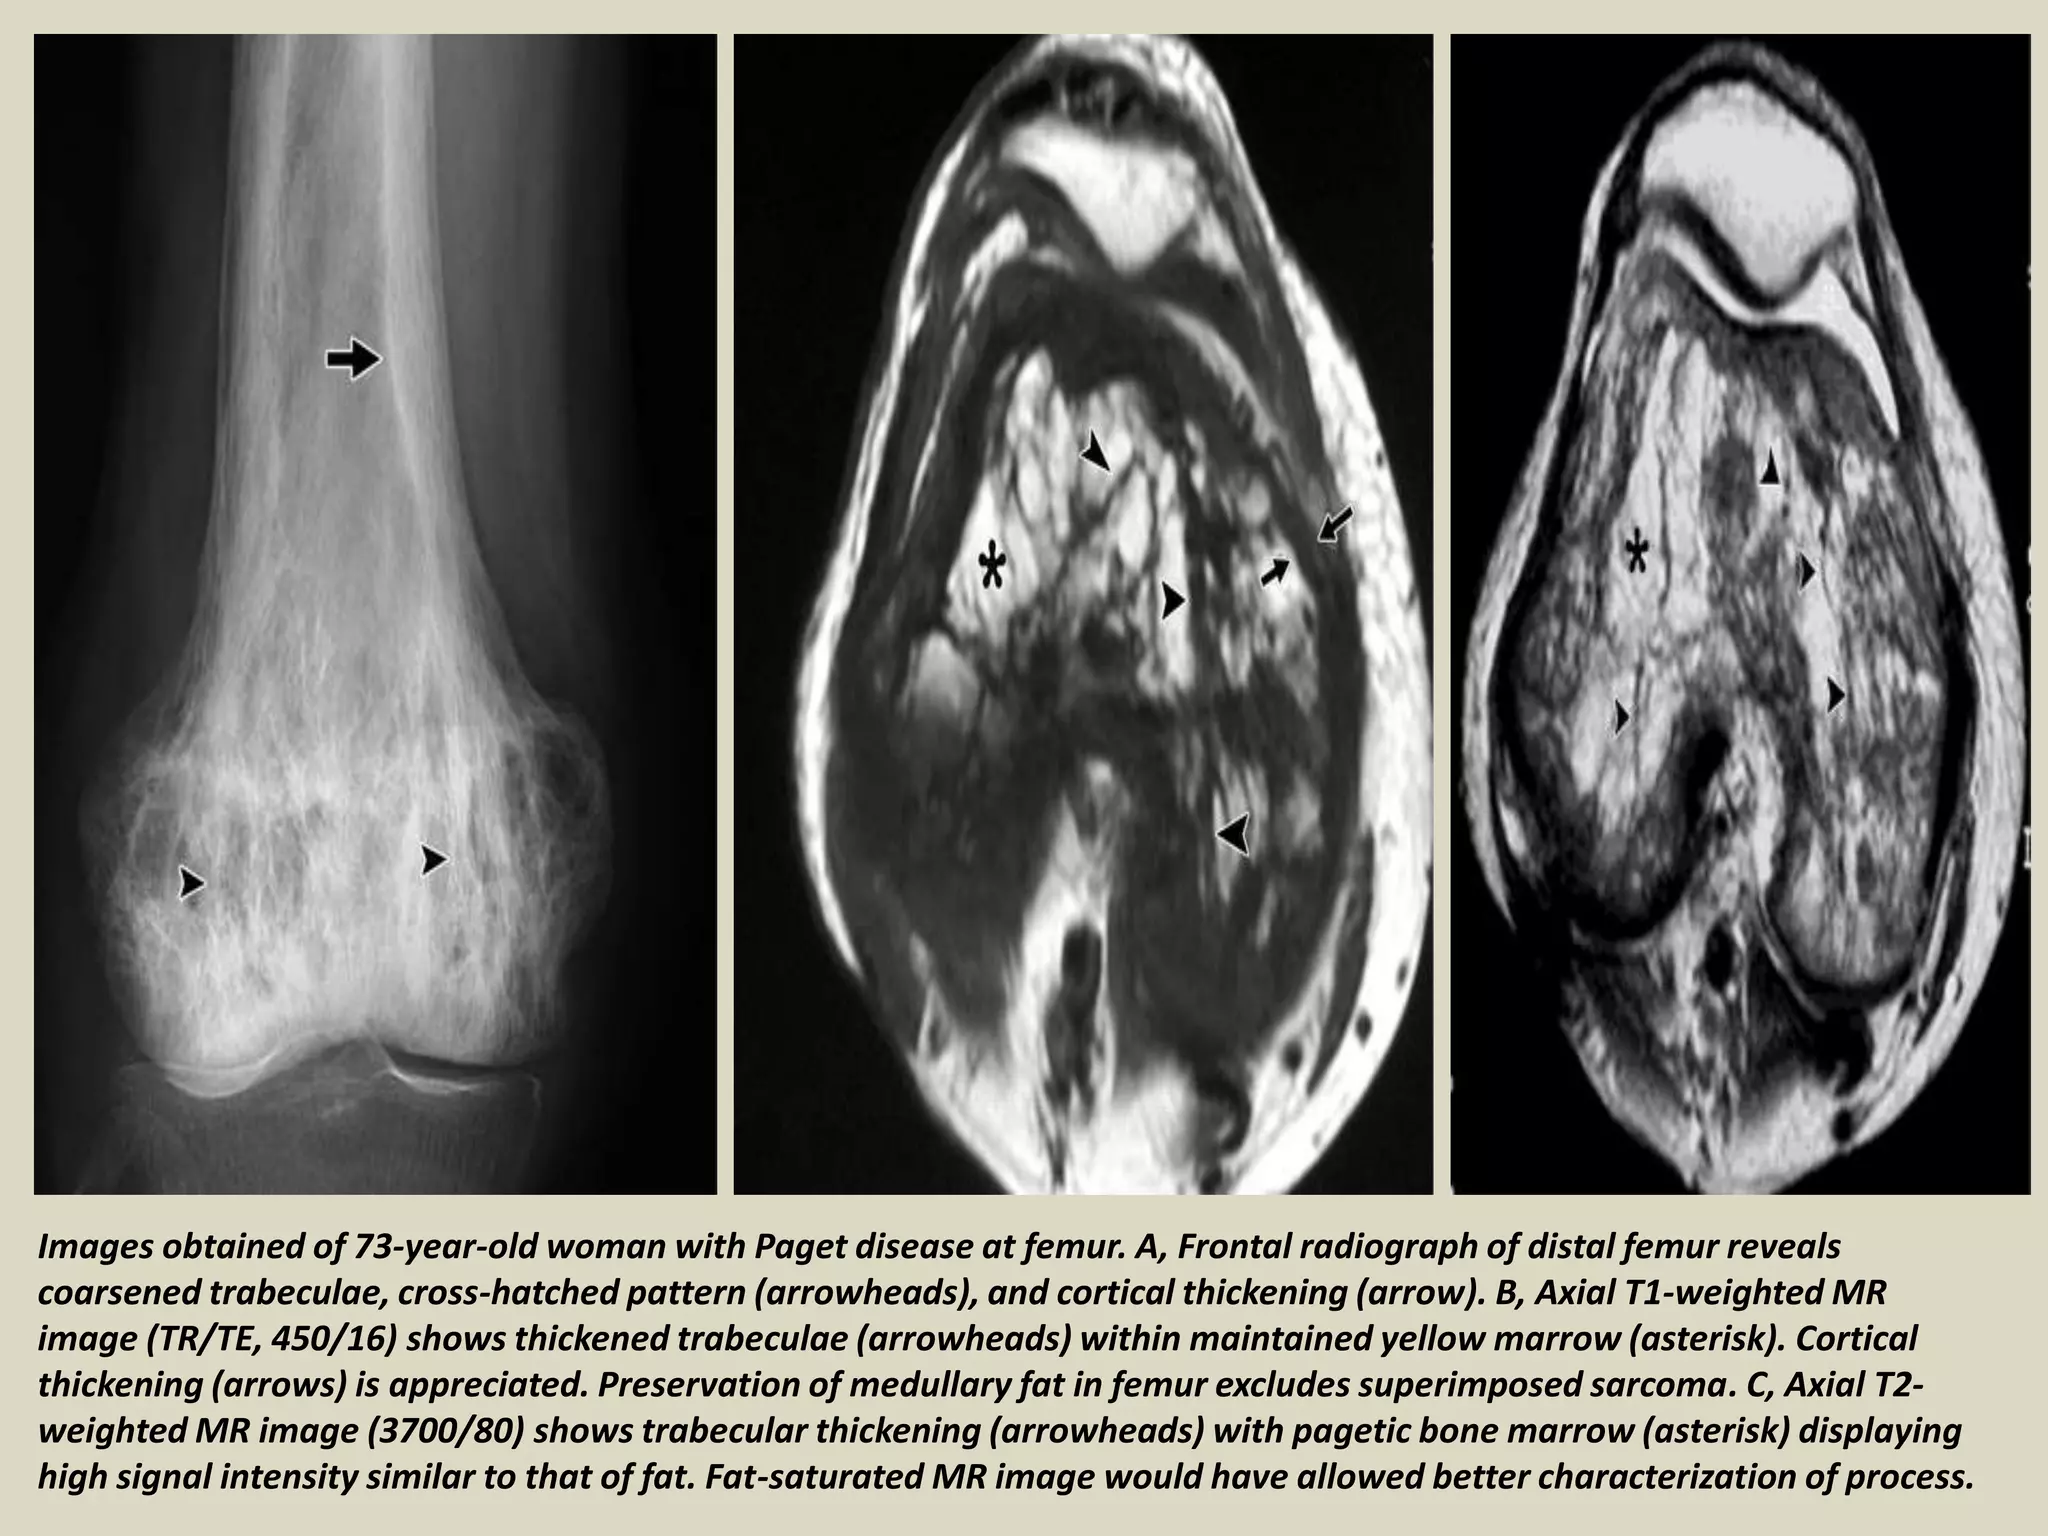

Images obtained of 73-year-old woman with Paget disease at femur. A, Frontal radiograph of distal femur reveals

coarsened trabeculae, cross-hatched pattern (arrowheads), and cortical thickening (arrow). B, Axial T1-weighted MR

image (TR/TE, 450/16) shows thickened trabeculae (arrowheads) within maintained yellow marrow (asterisk). Cortical

thickening (arrows) is appreciated. Preservation of medullary fat in femur excludes superimposed sarcoma. C, Axial T2-

weighted MR image (3700/80) shows trabecular thickening (arrowheads) with pagetic bone marrow (asterisk) displaying

high signal intensity similar to that of fat. Fat-saturated MR image would have allowed better characterization of process.